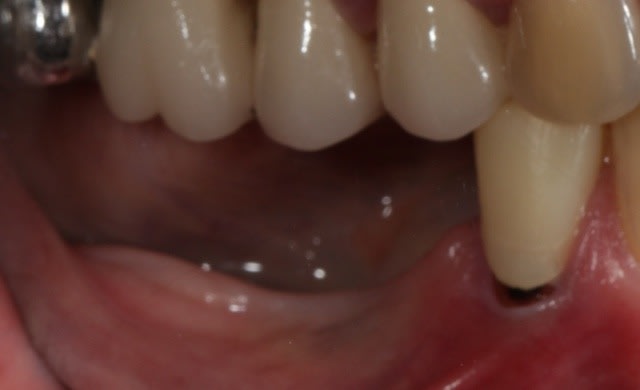

A J+7 ça a l'air de bien se présenter.

http://focusimplant-unitaire-posterieur.com/